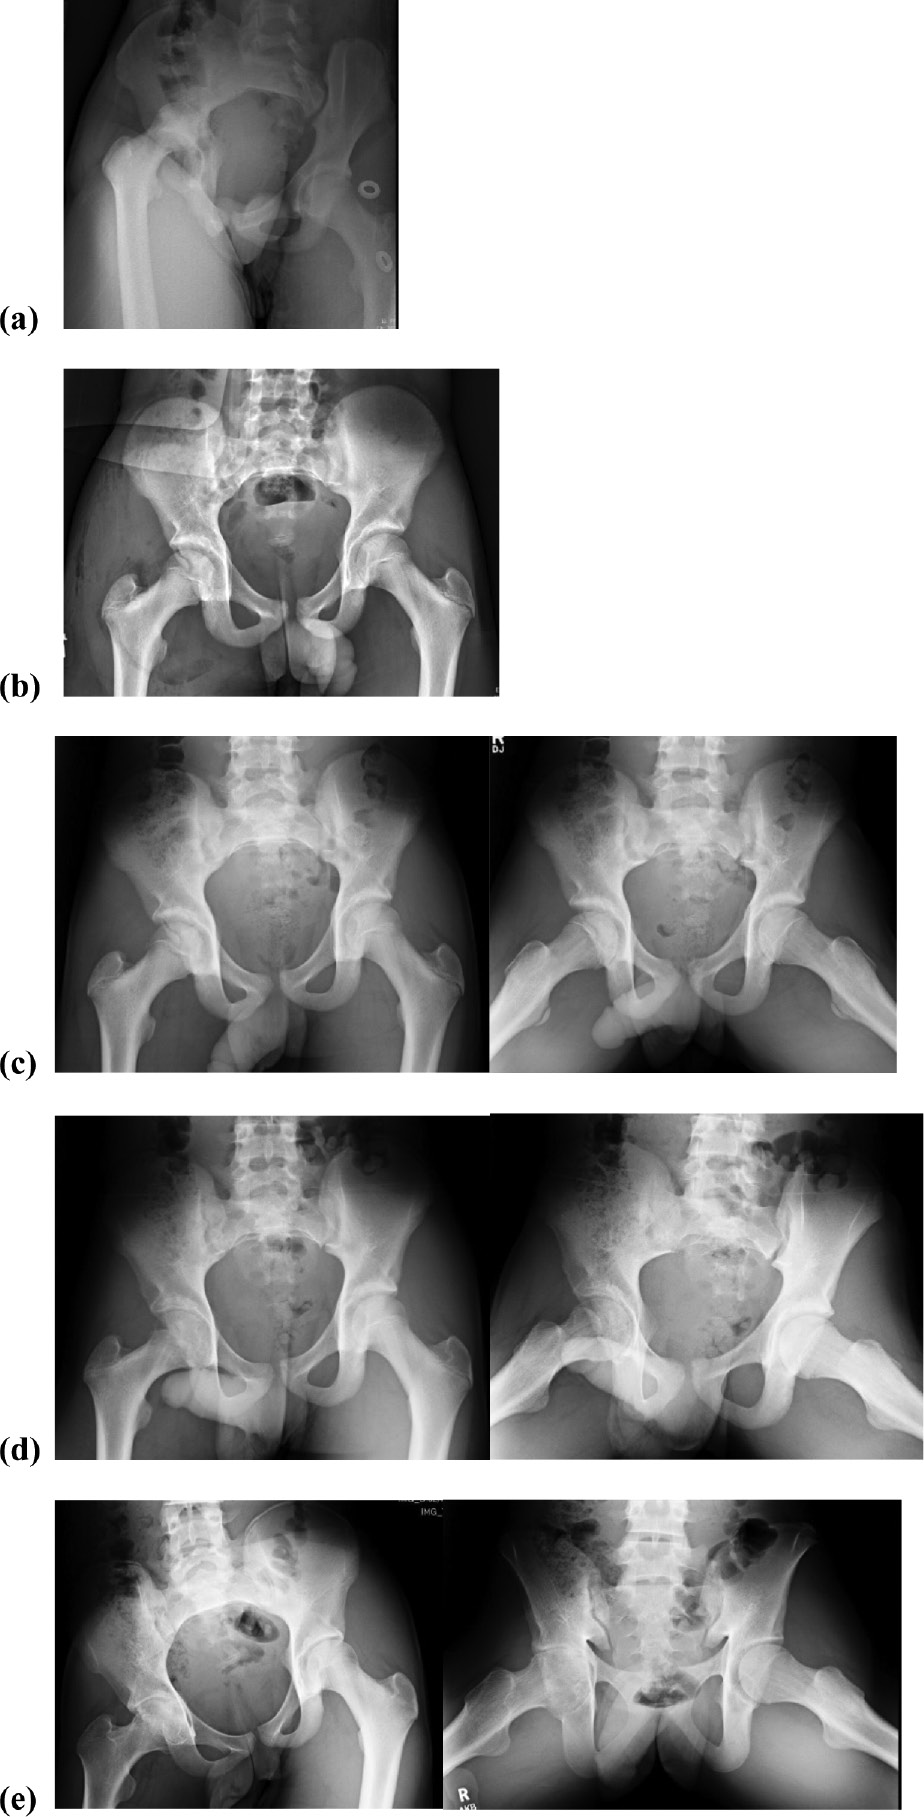

One patient, a skeletally immature 14-year-old male, developed joint space narrowing and chondrolysis following hip arthroscopy. His clinical course is depicted in Figure 5. This patient sustained a posterior hip dislocation as a result of an MVC and underwent a successful single attempt closed reduction under sedation 4 hours following time of injury. Postreduction radiographs revealed a nonconcentric reduction and CT demonstrated a posterior wall acetabular fracture with intraarticular chondral fragment. On post-injury day 1, he underwent exam under anesthesia, hip arthroscopy, anterior and posterior labral repair, chondral loose body removal (12 mm × 6 mm), and microfracture of the anterior acetabulum. The loose body was a full-thickness chondral injury of the anterior acetabulum at the 2-3 o’clock position. Postoperatively, he was treated with protected weight-bearing for 8 weeks, an abduction pillow, and posterior hip precautions. Physical therapy was initiated at 2 weeks postoperative for gentle hip range of motion. At 6 months postoperatively, he was noted to have joint space narrowing on radiographs and a decline in his hip motion. Inflammatory labs were normal and MRI was consistent with chondrolysis and no evidence for infection. He had transient improvement in symptoms with an intraarticular corticosteroid injection, but ultimately, he had progressive joint space narrowing, limited and painful motion, and was referred for hip arthroplasty 21 months post-injury.

Figure 5. 14-year-old male s/p MVC with right posterior hip dislocation (a). This was treated with prompt closed reduction in the emergency room with sedation (b) and subsequent hip arthroscopy with loose body removal, microfracture of the acetabulum, and posterior labral repair. A well-reduced concentric joint is noted at 2 weeks postop (c). At 6 months postop (d), there has been concentric joint space narrowing consistent with chondrolysis. At 20 months postop (e), there is significant pelvic tilt and progressive near complete joint space loss with coxa profunda.